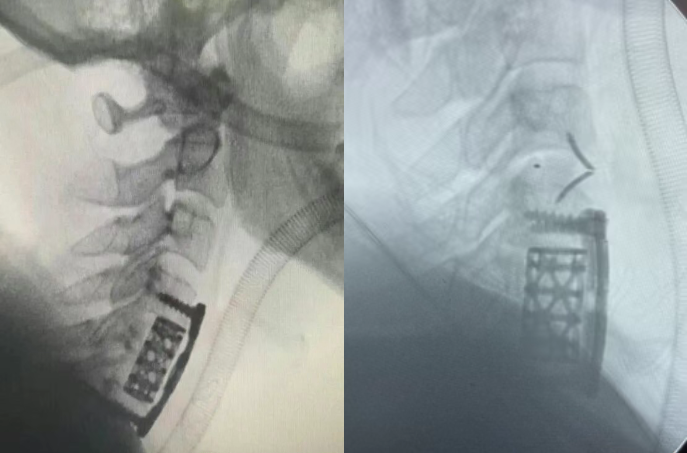

应用效果展示:

ACCF术中需要切除病变椎体的大部分,仅保留椎体侧方边缘部分,术中还需要做头端、尾端椎间盘的切除,减压结束后取合适长度的钛网支撑(钛网植入自体或异体骨粒),最后钛板螺钉固定。

ACCF的内固定稳定强度不足,术后钛网沉降、钛板移位、螺钉断裂松动的可能性更大,有文献报道ACCF术后,有10%~40%的患者存在钛网下沉情况。

较为严重的钛网下沉将带来一系列相关并发症,如肩背部疼痛、神经损伤、肢体运动障碍等,甚至需要二次手术治疗。造成钛网下沉的因素中,钛网倾斜角度、钛网与终板的接触面积等可以用过优化产品选择来尽量避免。